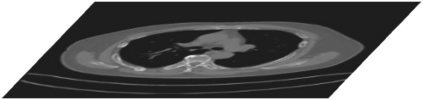

Rib fractures are a common and potentially severe injury that can be challenging and labor-intensive to detect in CT scans. While there have been efforts to address this field, the lack of large-scale annotated datasets and evaluation benchmarks has hindered the development and validation of deep learning algorithms. To address this issue, the RibFrac Challenge was introduced, providing a benchmark dataset of over 5,000 rib fractures from 660 CT scans, with voxel-level instance mask annotations and diagnosis labels for four clinical categories (buckle, nondisplaced, displaced, or segmental). The challenge includes two tracks: a detection (instance segmentation) track evaluated by an FROC-style metric and a classification track evaluated by an F1-style metric. During the MICCAI 2020 challenge period, 243 results were evaluated, and seven teams were invited to participate in the challenge summary. The analysis revealed that several top rib fracture detection solutions achieved performance comparable or even better than human experts. Nevertheless, the current rib fracture classification solutions are hardly clinically applicable, which can be an interesting area in the future. As an active benchmark and research resource, the data and online evaluation of the RibFrac Challenge are available at the challenge website. As an independent contribution, we have also extended our previous internal baseline by incorporating recent advancements in large-scale pretrained networks and point-based rib segmentation techniques. The resulting FracNet+ demonstrates competitive performance in rib fracture detection, which lays a foundation for further research and development in AI-assisted rib fracture detection and diagnosis.